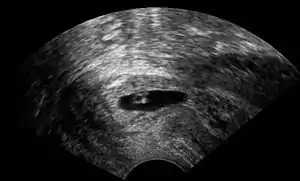

Vaginal ultrasonography of a cervical pregnancy at a gestational age of five weeks. See image below for details of the visible structures.[1]

The diagnosis is made in asymptomatic pregnant women either by inspection seeing a bluish discolored cervix or, more commonly, by obstetric ultrasonography. A typical non-specific symptom is vaginal bleeding during pregnancy. Ultrasound will show the location of the gestational sac in the cervix, while the uterine cavity is "empty". Cervical pregnancy can be confused with a miscarriage when pregnancy tissue is passing through the cervix.